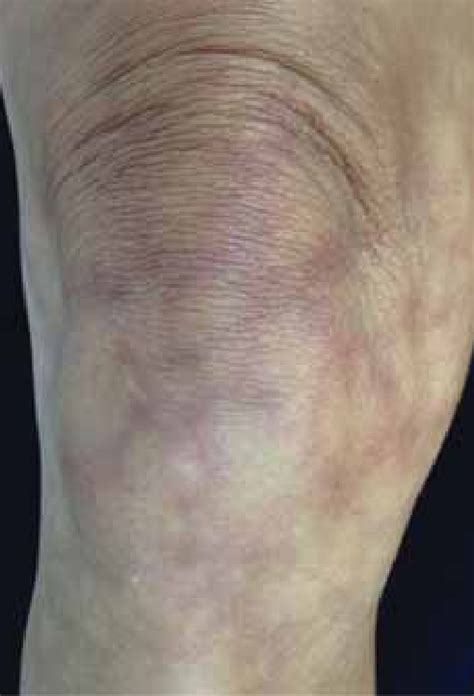

Livedo reticularis is characterized by its unique appearance, which resembles a lace or fishnet pattern on the skin. It is caused by the slowing down or reduction of blood flow to the skin, which leads to the visibility of the blood vessels through the skin, creating the distinctive mottled appearance. This condition can affect various parts of the body, including the arms, legs, and torso. Livedo reticularis photos showcase the variability in presentation, from mild, barely noticeable changes to more pronounced, widespread discoloration.

The causes of livedo reticularis can be broadly categorized into primary and secondary. Primary livedo reticularis is often benign and idiopathic, meaning its cause is unknown, and it may be influenced by cold temperatures or other environmental factors. Secondary livedo reticularis, however, is associated with underlying medical conditions, such as autoimmune diseases (e.g., lupus, rheumatoid arthritis), vasculitis, and neurological disorders. Certain medications and infections can also lead to livedo reticularis. A thorough examination of livedo reticularis photos can help differentiate between the primary and secondary forms, guiding further diagnostic investigations.

Diagnosing livedo reticularis involves a combination of clinical examination, medical history, and sometimes, additional diagnostic tests to rule out underlying conditions. Livedo reticularis photos can aid in the initial assessment, helping to identify the characteristic pattern and distribution of the discoloration. Management strategies depend on the underlying cause; for primary livedo reticularis, measures to improve circulation and protect the skin from cold may be sufficient. For secondary livedo reticularis, treatment focuses on addressing the associated medical condition, which may involve medication, lifestyle changes, or other interventions.